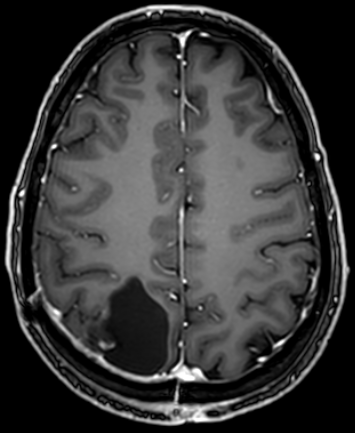

The following picture is the result after surgery.

The protocol was started shortly before radiotherapy and chemotherapy, which lasted for 1.5 months. He was essentially symptom free from the treatment. It was so remarkable that he was interviewed because of it.

The MRI after 3 months, shown below, is encouraging. No relapse so far.